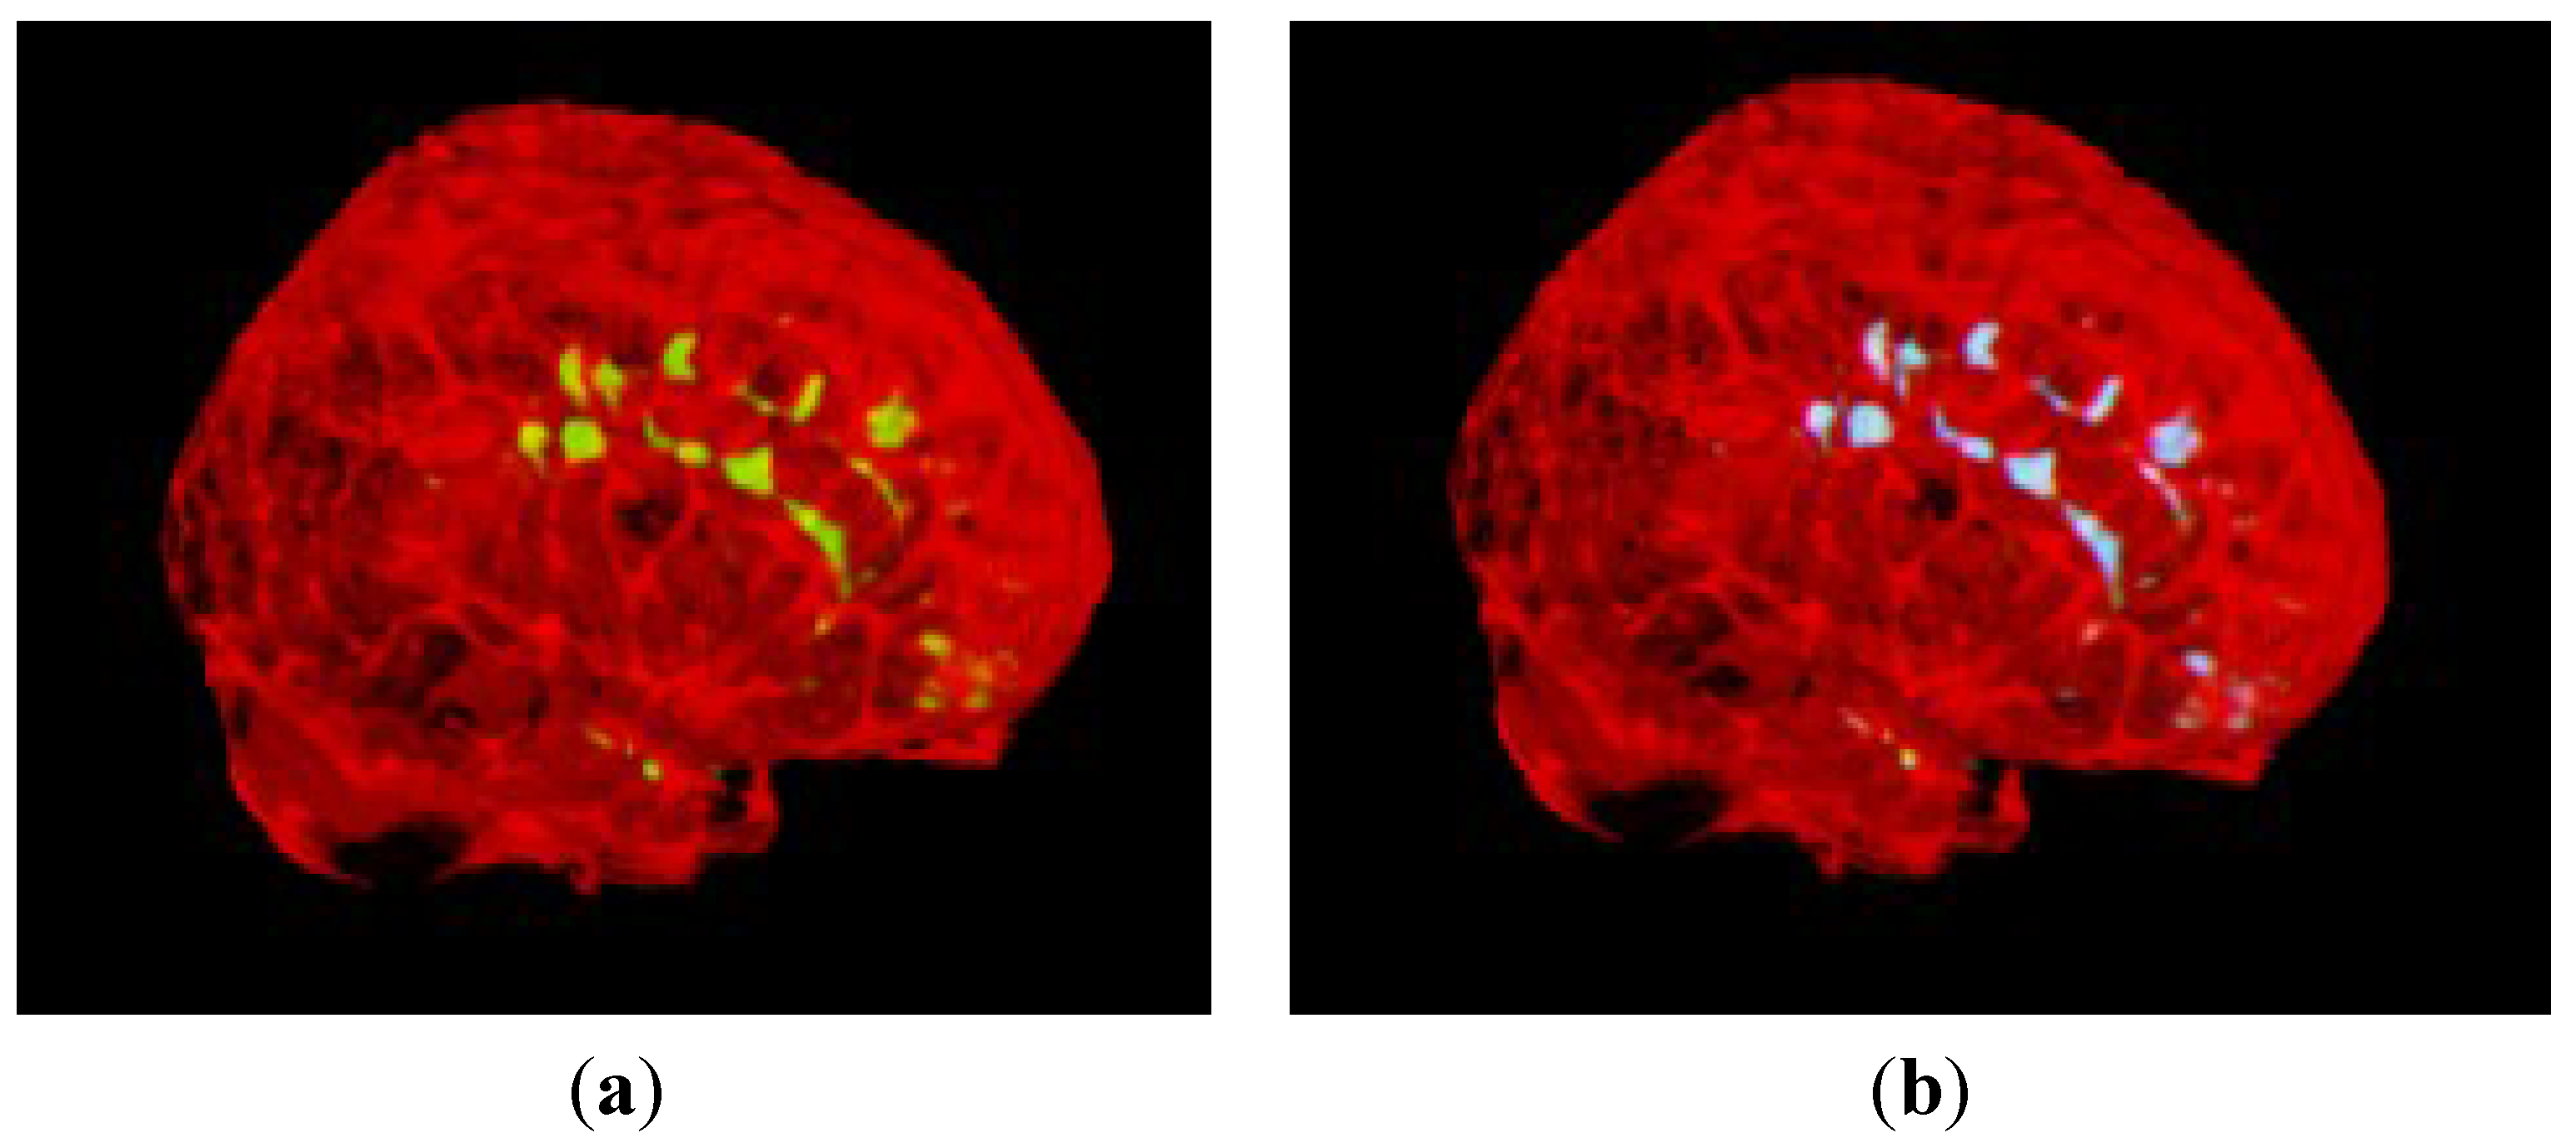

3.2. Segmentation of MS Lesions in a Whole Brain Volume

3.2.1. Brain Data with Mild MS Lesions